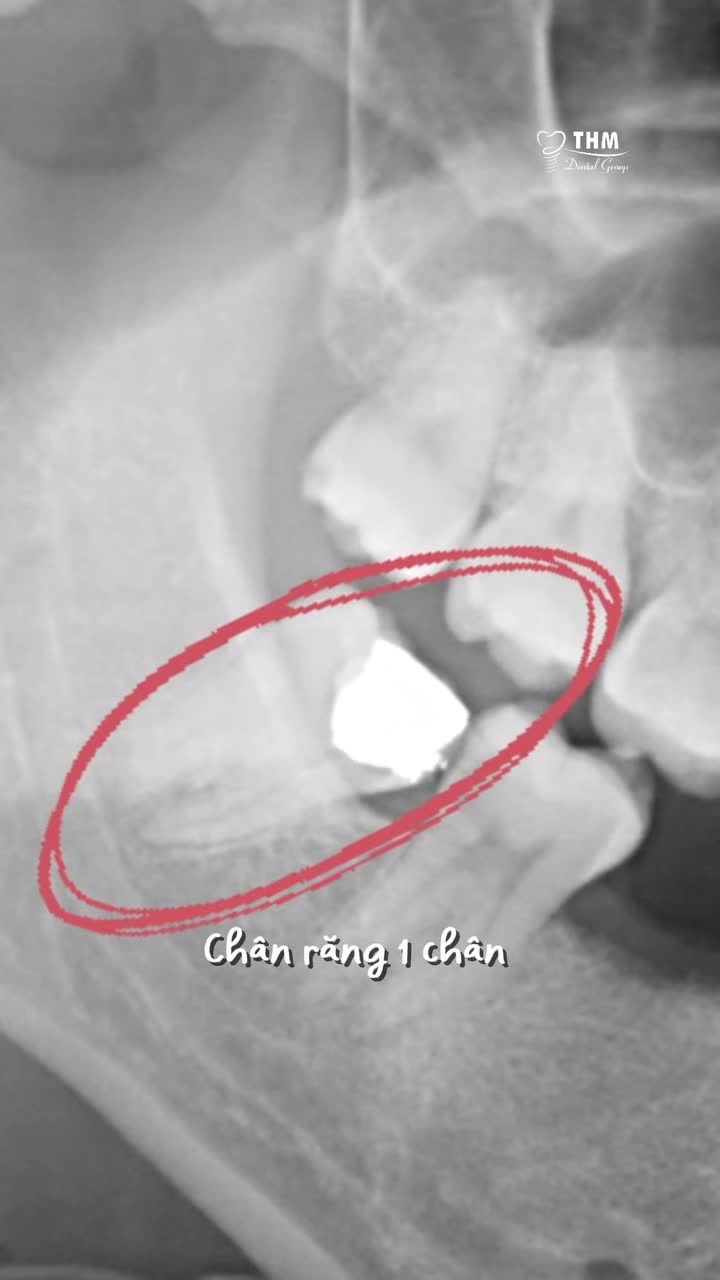

Những lưu ý khi di gần răng 7 và 8 trong trường hợp mất răng 6.